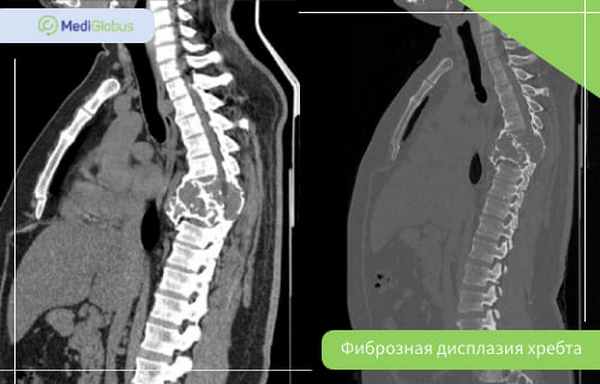

Фиброзная дисплазия позвоночника

Фиброзная дисплазия позвоночника встречается в 2,5% случаев болезни; чаще – в полиоссальной форме. Шейные позвонки поражаются в два раза реже, чем поясничные.

Фиброзная дисплазия хребта может стать причиной сколиоза – бокового искривления позвоночника. В редких случаях из-за поражения позвонков защемляется нерв. В зависимости от того, в каком отделе хребта это произошло, будут отличаться симптомы. Среди них самые распространенные:

Так как главный симптом при поступлении в больницу – это спинная боль, в первую очередь пациентам назначают МРТ и КТ. При подозрении на фиброзную дисплазию могут назначить биопсию, особенно пациентам взрослого или пожилого возраста.